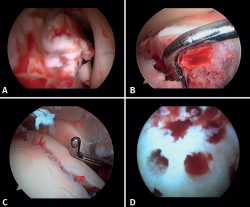

- Manejo de las lesiones condrales: la bibliografía reporta tasas entre el 34 y el 91% de estas lesiones en las fracturas de tobillo. Estas lesiones se localizan frecuentemente en el astrágalo y son más comunes en fracturas graves, como las fracturas Weber C y PER. Los pacientes con lesiones del cartílago tuvieron una probabilidad 3,5 veces mayor de desarrollar osteoartritis radiográfica (puntuación de artritis de Kannus < 90) y un riesgo 5 veces mayor de presentar un pronóstico clínico a largo plazo desfavorable (puntuación de la American Orthopaedic Foot and Ankle Society –AOFAS– < 90)(14).

Si es posible, realizaremos la reinserción de fragmentos osteocondrales inestables (Figura 3). En las lesiones condrales donde no es posible reinsertar el fragmento, pueden emplearse técnicas de estimulación de reparación del cartílago(5,13).

Figura 3. A: cuerpos libres; B: lesión osteocondral; C: reducción de la lesión osteocondral; D: estimulación medular.